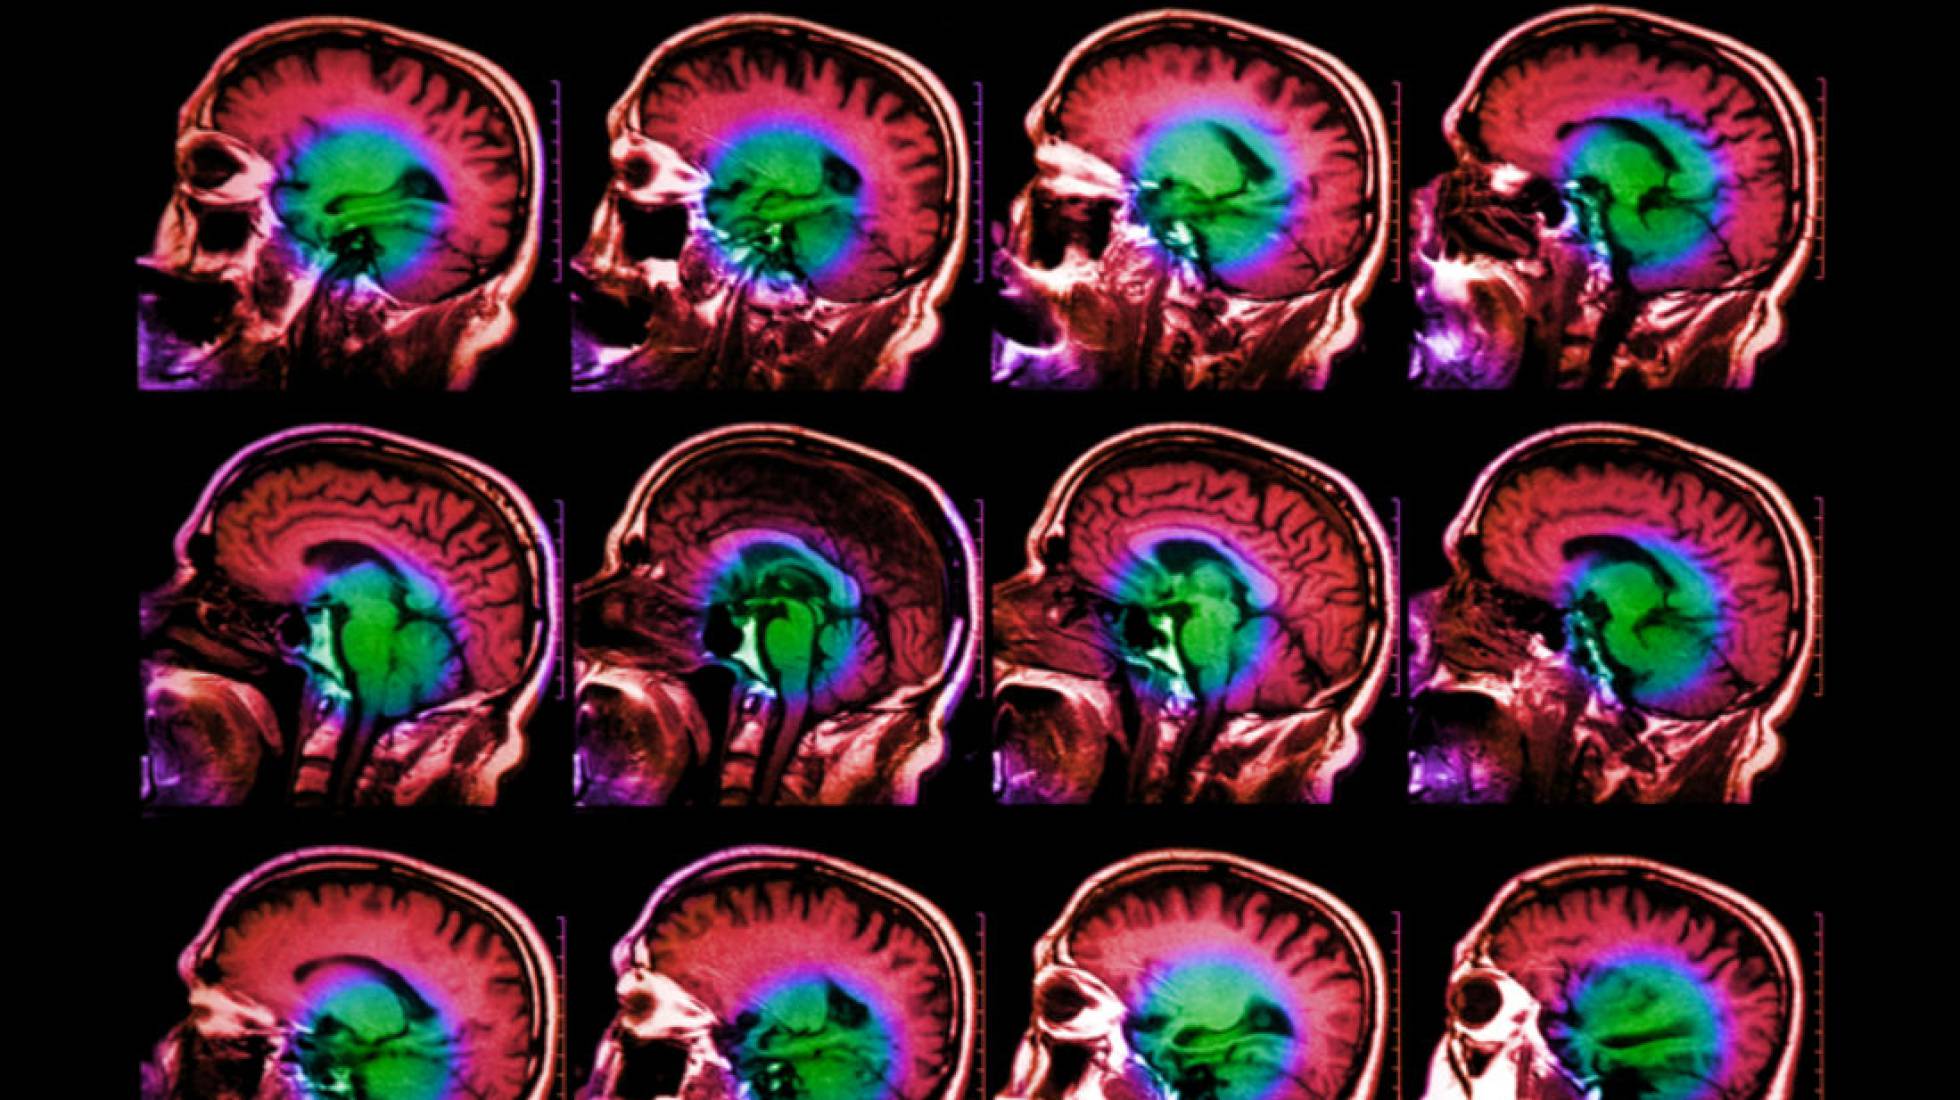

La muerte de neuronas, la pérdida de control de los movimientos, falta de equilibrio, demencia. Es larga la lista de problemas provocados por la factura biológica que el tiempo cobra al cerebro. Pero, ¿qué provoca el envejecimiento cerebral? Investigadores del Centro Médico de la Universidad de Columbia, en Estados Unidos, han descubierto un gen que tiene relación directa con ese problema y que, a partir de los 65 años, influye en el riesgo de enfermedades neurodegenerativas.

Los científicos Asa Abeliovich y Herve Rhinn analizaron el material genético de 1.904 muestras de cerebros humanos sanos e identificaron un gen llamado TMEM106B, cuyas variantes interfieren en el córtex frontal, la región responsable de la mayor parte de la actividad cerebral. "Si miras a un grupo de ancianos, algunos parecerán mayores que otros. Lo mismo ocurre con el esa región del cerebro. Nuestros resultados muestran que las personas que poseen variantes de riesgo de ese gen tienen un córtex frontal que parece 12 años mayor que el de otra que tenga variantes protectores", explica Rhinn a EL PAÍS. Su hipótesis, publicada en la revista científica Cell Systems, es que TMEM106B es parte de una red de resiliencia que determina cómo el cerebro hace frente a los factores de estrés relacionados con la edad.

Distintos genes que aumentan el riesgo de una persona de desarrollar una enfermedad neurodegenerativa ya aparecían en estudios anteriores. Un ejemplo es el gen APOE, que se relaciona con la aparición de la enfermedad de Alzheimer. Abeliovich y Rhinn sostienen que la novedad de su trabajo es el hallazgo de una variante genética que modula el ritmo en el que el cerebro envejece. "De lejos, el principal factor de riesgo para la enfermedad neurodegenerativa es el envejecimiento. Algo cambia en el cerebro a lo largo de los años que te hace más susceptible a enfermedades cerebrales. Nuestro objetivo era investigar qué factores genéticos conducen al envejecimiento", dice Rhinn.

Para ello, los investigadores examinaron los transcriptomas (es decir, las moléculas iniciales de la expresión genética) de las 1.904 muestras para obtener una imagen promedio del cerebro de un individuo de determinada edad. Después, compararon cada material con el transcriptoma correspondiente a su edad, buscando específicamente alrededor de 100 genes cuya expresión se incrementaba o disminuya durante el envejecimiento. A partir de esta comparación, llegaron al concepto de envejecimiento diferencial: la diferencia entre la edad aparente (biológica) de un individuo y su edad verdadera (cronológica) e identificaron el TMEM106B como responsable por esa edad diferencial. Se trata de un gen cuyas variantes están muy repartidas: "Una tercera parte de la población tiene dos copias de ese gen y otra tercera parte tiene una copia", afirma Rhinn.